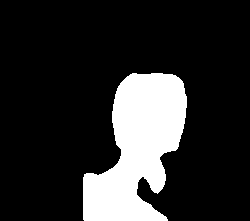

A few sample images and the corresponding masks of the polyp dataset in HyperKvasir are shown in Fig 2. The polyp images are RGB images. The masks of the polyp images are single-channel images with white () for true pixels, which represent polyp regions, and black () for false pixels, which represent clean colon or background regions. In this dataset, there are different sizes of polyps. The distribution of polyp sizes as a percentage of the full image size is presented in the histogram plot in Fig 3, and we can observe that there are more relatively small polyps compared to larger polyps. Additionally, a subset of this dataset was used to prove that the performance of segmentation models trained with small datasets can be improved using our SinGAN-Seg pipeline, and the whole dataset was used to show the effect of using SinGAN-Seg generated synthetic images instead of a large dataset which has enough data to train segmentation models. In this regard, this dataset was used for two purposes:

After training SinGAN-Seg models, we generated random samples per real image using the input scale , which is the lowest scale that uses a random noise input instead of a re-scaled input image. For more details about these scaling numbers and corresponding output behaviors, please refer to the vanilla SinGAN paper [56]. Three randomly selected training images and the corresponding first synthetic images generated using scale are depicted in Fig 4. The first column of the figure represents the real images and the ground truth mask annotated from experts. The rest of the columns represent randomly generated synthetic images and the corresponding generated mask.

In total, we have generated synthetic polyp images and the corresponding masks. SinGAN-Seg generates random samples with high variations when the input scale is . This variation can be easily recognized using the standard deviation (SD) and the mean mask images presented in Fig 5. The mean and SD images were calculated by stacking the generated mask images corresponding to the synthetic images related to a real image and calculating pixel-wise std and mean. Bright color in std images and dark color in mean images mean low variance of pixels. In contrast, dark color in std and bright color in mean images reflect high variance in pixel values. By investigating Fig 5, we see that small polyp masks have high variance compared to the large polyp mask as presented in the figure.